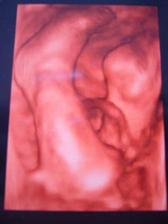

12.11.2008 nám pani doktorka potvrdila, že bábätko v brušku bude naša malá Nikolka, ktorá sa nám narodila 20.feb. 2009